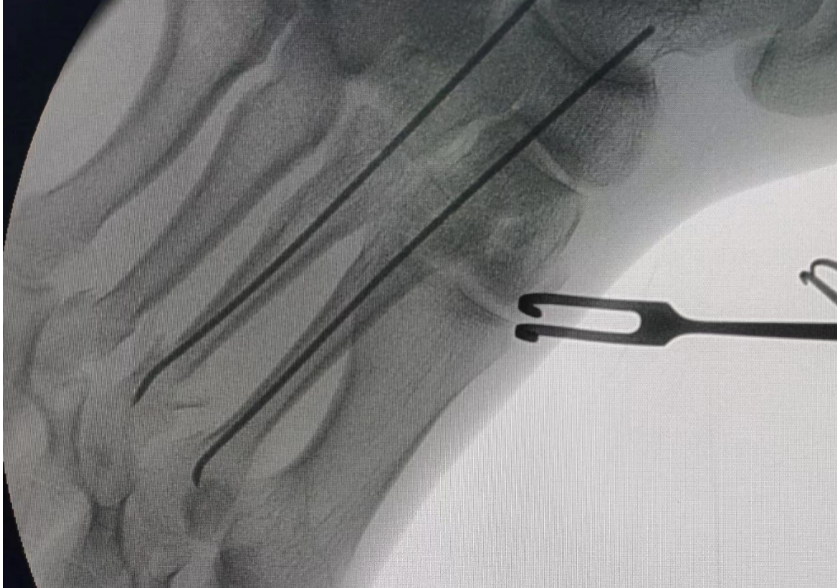

根据文献,建议对任何移位大于3-4 mm,角度大于10°的骨折进行复位。【3】首推小切口的手术方式,因为大切口往往会影响跖骨周围的血运以及较高的切口并发症。用髓内克氏针固定时目前认为的金标准,逆行髓内固定是治疗单纯性中间跖骨骨折最常见的方法。克氏针应通过跖骨头或相对应的的近端趾骨基部插入。

Baumfeld等人提出顺行克氏针髓内固定方法来替代逆行克氏针髓内钉技术,并且认为,顺行置入克氏针相较于逆行技术具有感染率低,软骨破坏程度小等优势,术后6周完全负重,克氏针将会在术后6-8周。